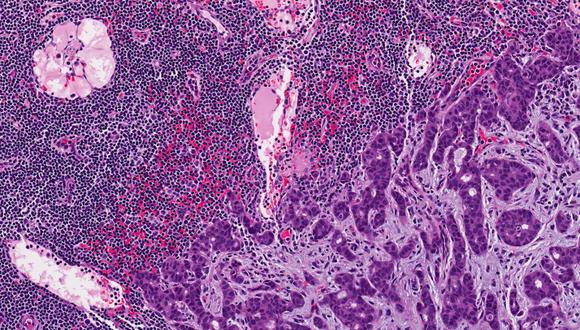

בתגלית פורצת דרך גילו חוקרים מאוניברסיטת תל אביב את מנגנון ההתפשטות של גרורות של מנלומה, סרטן העור האגרסיבי ביותר. החוקרים מצאו כי לפני שמלנומה מתפשטת, היא שולחת בועיות זעירות המכילות חומר גנטי מסוג מיקרו RNA, והן שיוצרות את השינוי במבנה הדרמיס - כהכנה לקליטת התאים הסרטניים ולשינוע הגרורות. החוקרים מצאו גם חומרים שיכולים לעצור את התהליך אשר עשויים בעתיד לשמש כתרופה. המחקר התפרסם ביום שני, 22.9.16 בשעה 18:00, בכתב העת היוקרתי Nature Cell Biology כמאמר מוביל שאף זכה לתמונת שער בכתב העת.

"הסכנה במלנומה אינה בגידול הראשוני שמופיע על העור, אלא בגרורות שהסרטן שולח לאיברים חיוניים – כמו המוח, הריאות, הכבד והעצמות," מסבירה מובילת המחקר, ד"ר כרמית לוי מהמחלקה לגנטיקה של האדם וביוכימיה בבית הספר לרפואה של אוניברסיטת תל אביב. "במחקר שלנו גילינו כיצד הסרטן מתפשט לאיברים רחוקים, ואף מצאנו דרכים לעצור את התהליך לפני השלב הגרורתי."

החוקרים בחנו דוגמאות פתולוגיות שנלקחו מחולי מלנומה, והעלו ממצאים חדשים ומפתיעים. "הסתכלנו על דוגמאות של מלנומה ראשונית, לפני השלב הפולשני," אומרת ד"ר לוי. " להפתעתנו מצאנו שינויים שלא דווחו מעולם במבנה של השכבה התחתונה של העור, שנקראת דרמיס. משימתנו הבאה הייתה לברר מהם בדיוק השינויים הללו, וכיצד הם קשורים למלנומה." וכך, במחקר ארוך ומורכב, עלה בידי החוקרים לחשוף וגם לחסום מנגנון מרכזי ביצירת גרורות המלנומה.

לדבריה, ידוע שהמלנומה נוצרת בתחילתה בשכבה העליונה של העור, שנקראת אפידרמיס. בשלב ראשוני זה אין ביכולתו של הגידול לשלוח גרורות, כי באפידרמיס אין כלי דם – אותו 'כביש מהיר' שמוביל את תאי הסרטן אל איברים אחרים בגוף. כדי לשלוח גרורות, זקוק הגידול לקשר עם כלי הדם המצויים בשפע בדרמיס. אך כיצד נוצר הקשר? "גילינו שעוד לפני שהסרטן עצמו חודר לדרמיס, הוא שולח בועיות זעירות המכילות חומר גנטי מסוג מיקרו RNA, והן שיוצרות את השינוי במבנה הדרמיס - כהכנה לקליטת התאים הסרטניים ולשינוע הגרורות. הבנו שאם נצליח לחסום את הבועיות, נעצור את המחלה כולה." מסבירה ד"ר לוי.

ואכן, החוקרים לא הסתפקו בגילוי המנגנון, אלא בחנו וזיהו חומרים כימיים ספציפיים שיכולים להתערב ולעצור את התהליך בשלביו הראשוניים. חומר אחד (SB202190) מעכב את שליחת הבועיות מהגידול שבאפידרמיס אל שכבת הדרמיס; ואילו חומר אחר (U0126) מונע את היווצרות השינויים בדרמיס גם לאחר הגעת הבועיות. שני החומרים, שנוסו בהצלחה במחקר, יכולים לשמש כבסיס לפיתוח תרופות עתידיות למניעת מלנומה. בנוסף, השינויים שזוהו בדרמיס, וכן הבועיות עצמן, עשויים לשמש כסמנים מובהקים לאבחון מוקדם של הסרטן הקטלני.